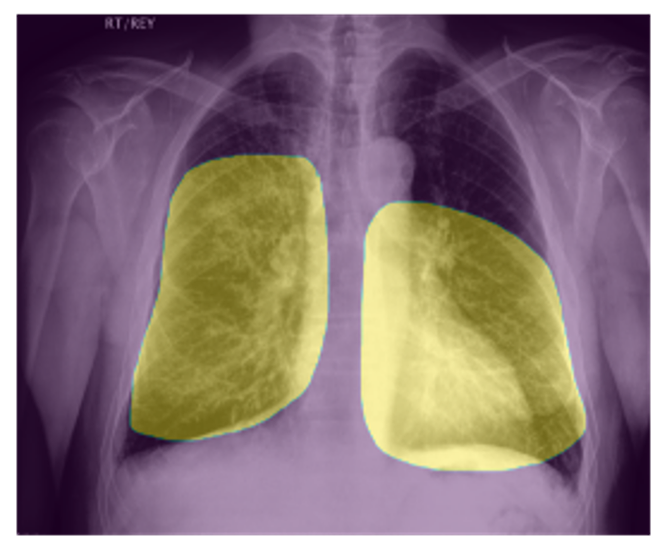

To delve deeper into the learned visual knowledge from IMITATE, we utilized Grad-CAM [57] to produce saliency maps for CXR images derived from the model in its pre-trained state. We select two CXR images showcasing two prevalent diseases, Edema and Lung Opacity. Notably, each of these images comes with ground truth annotation pinpointing the region of concern, as documented in [58]. As evident from Fig. 5, IMITATE boasts an impressive capability to accurately delineate the clinical regions of concern in the CXR images, outperforming its counterpart MGCA [4]. This is particularly noteworthy considering that IMITATE achieves this precision without relying on any external prompts or the need for additional model fine-tuning.